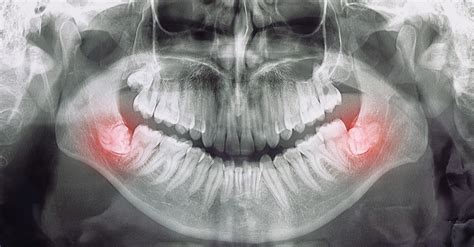

Radiografía mostrando la posición de las muelas del juicio.

Antes de la cirugía, es crucial una evaluación exhaustiva. El odontólogo examinará la boca y tomará radiografías panorámicas o 3D para evaluar la posición de las muelas del juicio y su relación con estructuras importantes como el hueso, los senos maxilares y el nervio dentario inferior. Esta información es vital para planificar la extracción de la manera más segura.